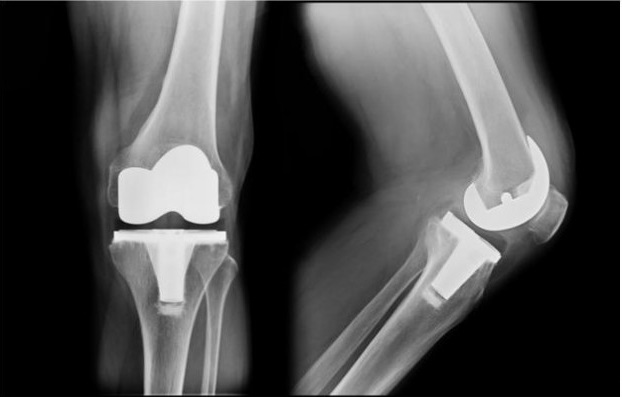

Η ολική αρθροπλαστική γόνατος είναι μια επέμβαση αντικατάστασης των φθαρμένων επιφανειών του αρθριτικού γόνατος. Αποτελεί λύση στην προχωρημένη μορφή αρθρίτιδας του γόνατος, ειδικά όταν έχουν αποτύχει άλλες συντηρητικές θεραπείες όπως φαρμακευτική αγωγή, ενδοαρθρικές ενέσεις ή φυσικοθεραπεία. Κατά την επέμβαση αντικαθίστανται οι κατεστραμμένες αρθρικές επιφάνειες με ειδικές μεταλλικές προθέσεις (εμφυτεύματα) και καθ’ αυτόν τον τρόπο επιτυγχάνεται ανακούφιση από τον πόνο και επαναφορά της φυσιολογικής κίνησης και λειτουργίας του γόνατος. Ιστορικά, οι πρώτες μοντέρνες ολικές αρθροπλαστικές γόνατος πραγματοποιήθηκαν την δεκαετία του 1970. Έκτοτε, η συνεχής πρόοδος και βελτίωση των τεχνικών και των υλικών την έχει καταστήσει μια επιτυχημένη και ασφαλής επέμβαση.

Η άρθρωση του γόνατος αποτελείται από το κατώτερο τμήμα του μηρού, το ανώτερο τμήμα της κνήμης και την επιγονατίδα. Συνήθως αντικαθιστούμε τις επιφάνειες του μηρού και τις κνήμης και λιγότερο συχνά την επιγονατίδα.

Η ολική αρθροπλαστική διαρκεί κατά κανόνα 1-1,5 ώρα και δύναται να πραγματοποιηθεί υπό περιοχική αναισθησία (ραχιαία ή επισκληρίδιο), η οποία και προτιμάται, ή υπό γενική αναισθησία. Αρχικά, σχεδιάζεται μια επιμήκης τομή στην πρόσθια επιφάνεια του γόνατος, το μήκος της οποίας εξαρτάται από τα χαρακτηριστικά του εκάστοτε ασθενούς και την βαρύτητα της αρθρίτιδας. Στη συνέχεια γίνεται προετοιμασία του οστού, όπου οι φθαρμένες αρθρικές επιφάνειες αφαιρούνται μαζί με ένα λεπτό τμήμα οστού και ακολουθεί η τοποθέτηση των μεταλλικών εμφυτευμάτων σε μηρό και κνήμη και ενός συνθετικού υλικού (πολυαιθυλένιο) αναμεσά τους. Η στερέωση των προθέσεων γίνεται είτε με την χρήση ορθοπεδικού τσιμέντου είτε τοποθετούνται απευθείας πάνω στο οστό και συγκρατούνται με τη διαδικασία της οστεοενσωμάτωσης, δηλαδή με λειτουργική και δομική σύνδεση οστού και εμφυτεύματος. Οι σύγχρονες προθέσεις προσφέρουν μακροχρόνια αντοχή της ολικής αρθροπλαστικής και επιτρέπουν επίπεδα δραστηριότητας σχεδόν ίδια με του φυσιολογικού γόνατος.